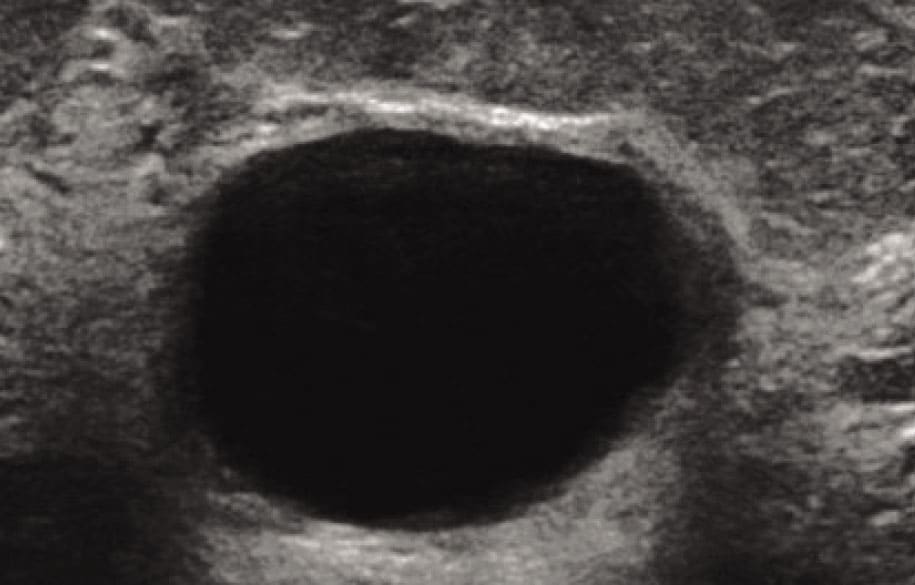

Слика 1.​

Ultrasound image of a simple tension cyst in the breast and image of content after puncture (about 45 ml of clear yellowish content was evacuated).